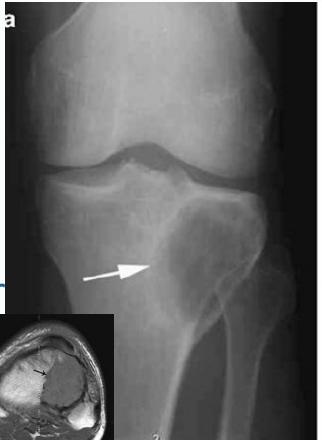

Osteoid Osteoma

- Small tumor (<1 cm)

- Young adults

- Pain, pain, pain:

- Typically relieved by Salicylates

- Sites: Femur, tibia, spine

- X-ray:

- Small radiolucent “nidus”

- Surrounded by sclerotic bone

- CT: Shows “nidus” better

- scan: hot

- Treatment: surgical excision, or thermal ablation

Source: Orthopedic Radiology. A Greenspan. Lippincott-Raven

Sources: Apley’s System of Orthop. And Fractures, http://openi.nlm.nih.gov/

Clinical Example

- 11 year old boy: Pain in left hip